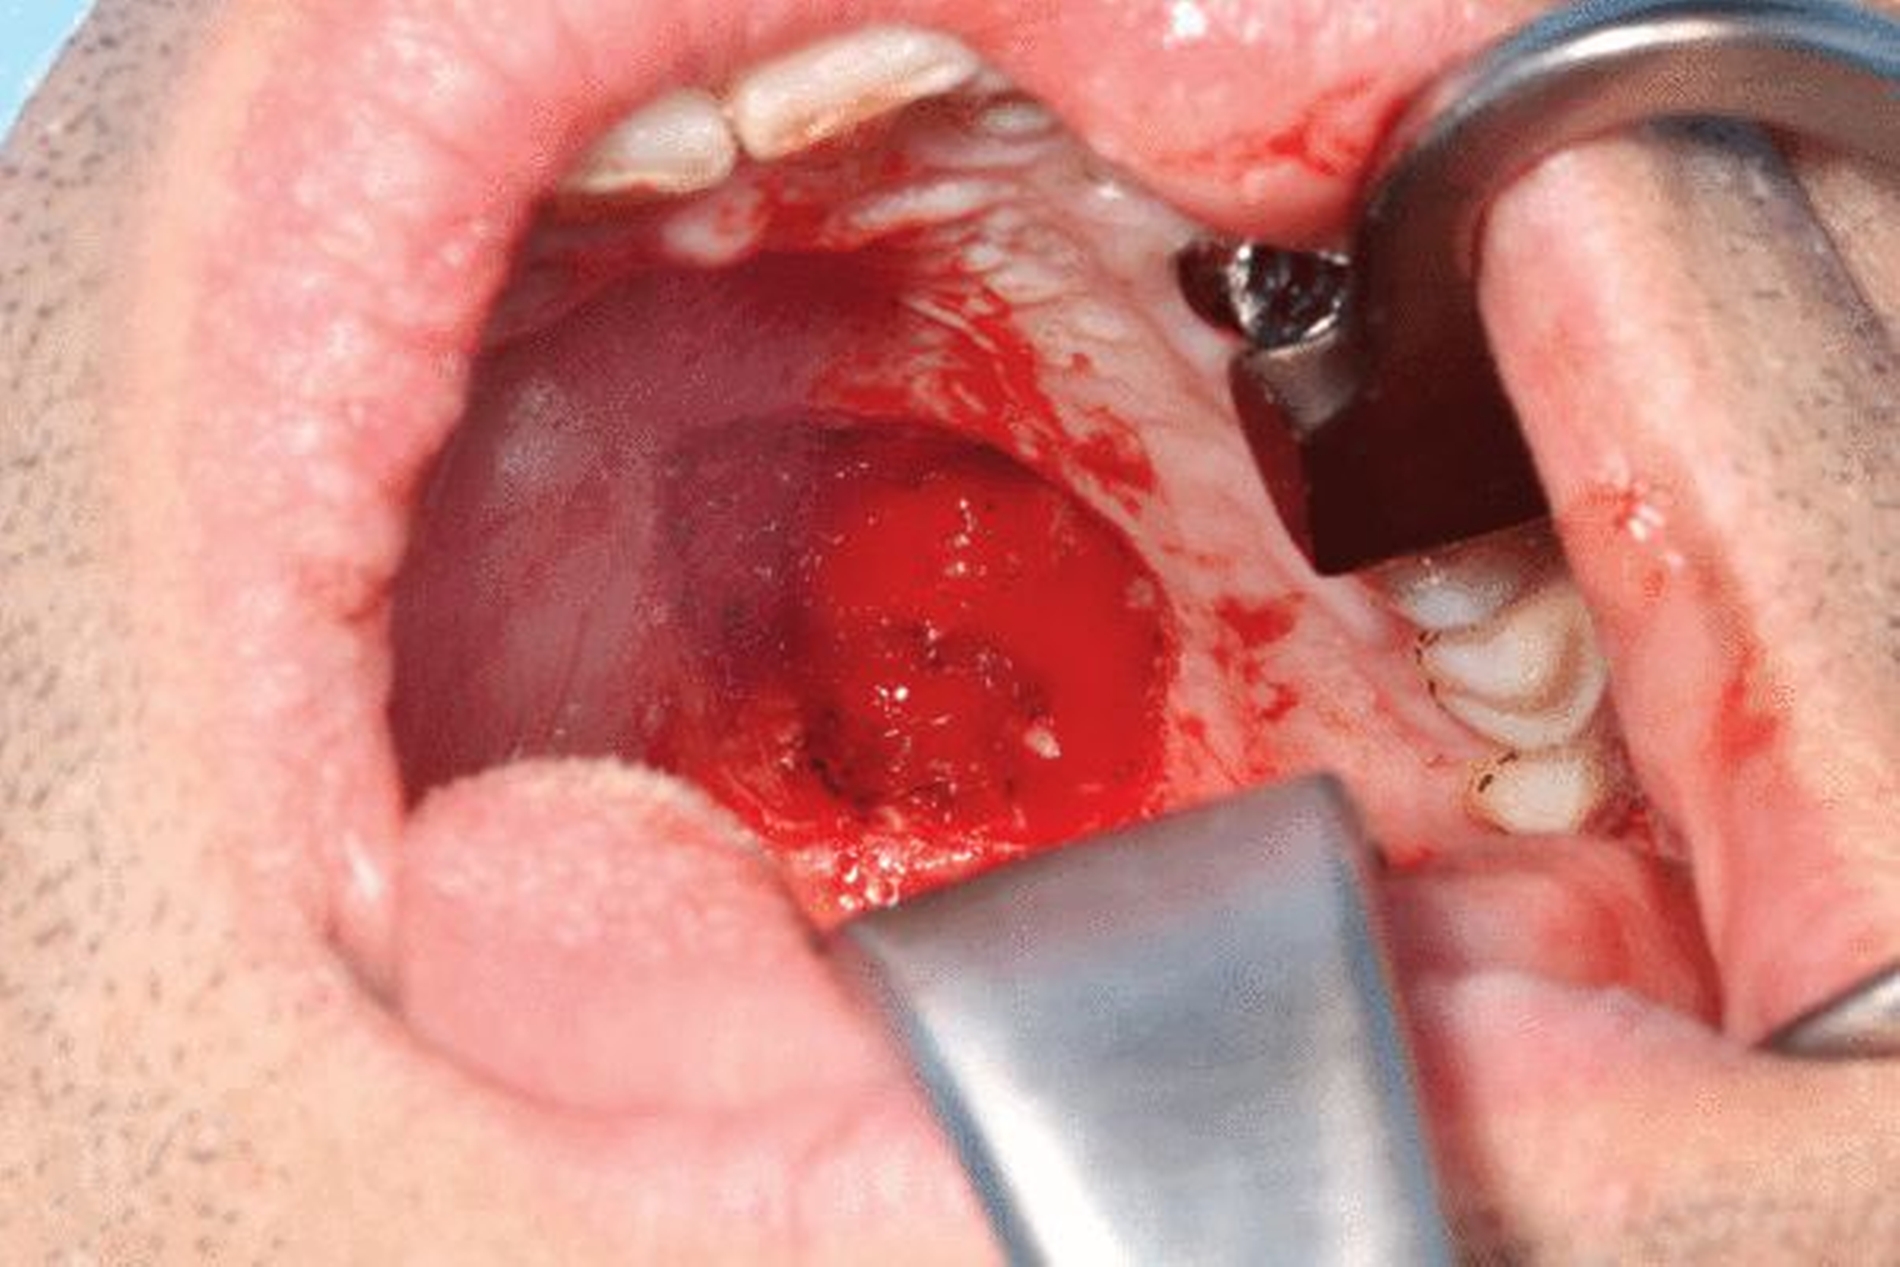

Zur weiteren Diagnostik und zur Beurteilung der Ausbreitung und der Infiltration des Befunds wurde eine Magnetresonanztomografie (MRT) durchgeführt. Hier zeigte sich eine submukosal gelegene, 8 mm x 10 mm x 8 mm große, glatt begrenzte, T1 hypertense, T2 inhomogen teils hypointense, teils isointense Raumforderung mit deutlichem Signalabfall in T2-Fettsättigung (Abbildung 2). Es bestand kein Hinweis auf knöcherne Infiltration. Daher wurde der Befund mit einem Sicherheitsabstand von 1 bis 2 mm unter Schonung des Nervus und der Arteria palatina major bis auf den palatinalen Knochen reseziert (Abbildung 3).